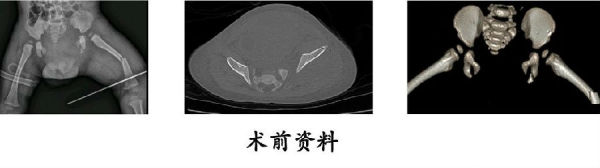

13.严某某,女,4岁,高处坠落伤(股骨颈、股骨干骨折),术后恢复颈干角、前倾角。